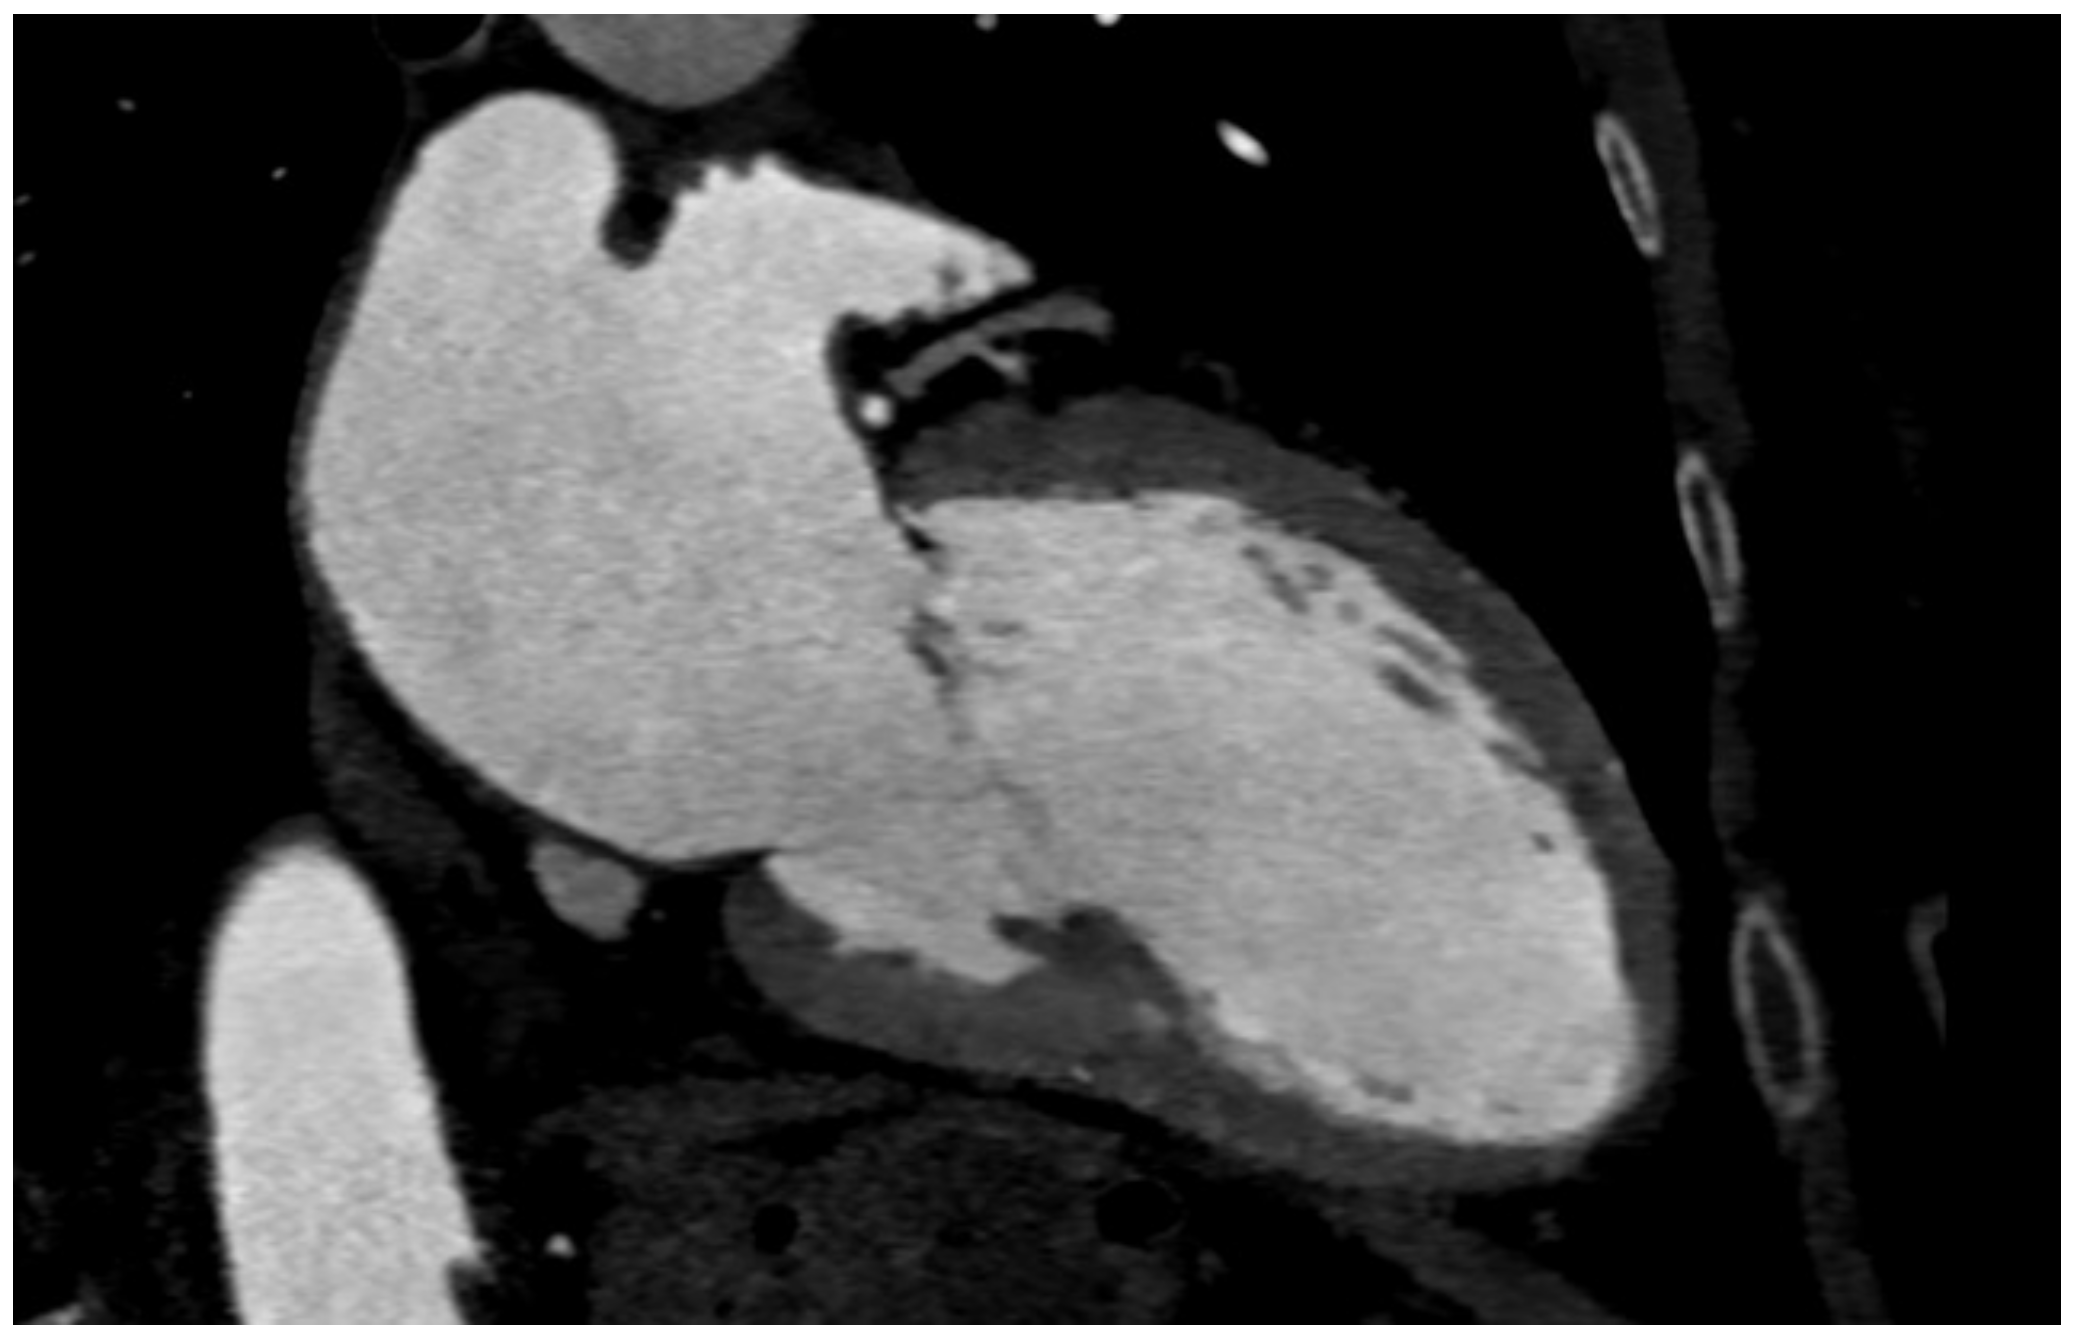

Both self-expandable and balloon-expandable THVs extend their lower extremity into the left ventricular outflow tract (LVOT). A careful assessment of this region should be performed to minimize complications (Figure 8a,b).

Figure 8.

(a) LVOT calcium degree evaluation. (b) Preoperative LVOT measurements.

The proper seating of the THV and the risk of spontaneous repositioning after deployment can be affected by marked upper septal hypertrophy protruding in LVOT. Furthermore, prominent septal hypertrophy is associated with atrioventricular blocks and the need for post-TAVI PMI [55]. Accordingly, Jilaihawi et al. showed that MDCT-based measurements of septal thickness predict the post-TAVI occurrence of AV blocks [56]. Septal hypertrophy causing significant LVOT obstruction is a contraindication to TAVI; however, as demonstrated by Moreno et al., proper modifications to THVs can allow successful implantation in this kind of patients [57]. Notably, Stolzmann et al. found that echocardiography tends to overestimate interventricular septum thickness compared with MDCT (up to 2.2 mm) [58] (Table 1).

Furthermore, the risk of significative residual aortic regurgitation and second valve implantation can be affected by moderate or severe LVOT calcification. In this regard, Okuno et al. proposed a specific classification based on the severity of LVOT calcification: mild was detected in the presence of one nodule extending <5 mm in any dimension and covering <10% of the perimeter of the LVOT; moderate was documented in the presence of two nodules or one extending >5 mm in any direction or covering >10% of the perimeter of the LVOT; and severe was considered in the case of multiple nodules of single focus extending >10 mm in length or covering >20% of the perimeter of the LVOT. Additionally, patients with moderate or severe LVOT calcification and treated with earlier-generation THVs suffered from an increased risk of annular rupture. The difference was not statistically significant among patients treated with newer generation prosthetic valves. Concordantly, it was observed that patients with moderate or severe LVOT calcification have an increased risk of death for all-cause mortality at one year [59].